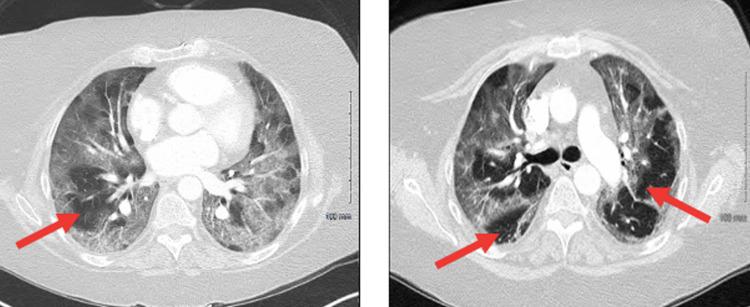

Remdesivir is an antiviral, nucleoside analog used extensively during the coronavirus-disease 2019 (COVID-19) pandemic with proven efficacy against COVID-19-induced acute respiratory distress syndrome (ARDS). Our case report details the clinical course of a 50-year-old, COVID-19-positive patient who developed sinus arrest after being treated with remdesivir. Within 24 hours of discontinuing remdesivir therapy, the patient's sinus arrest resolved to a normal sinus rhythm. The findings from our case report add to a growing body of evidence on the cardiotoxic profile of remdesivir. Remdesivir's ability to cause bradyarrhythmias, and specifically sinus arrest, should be acknowledged when considering the use of this drug in at-risk patients.

瑞德西韦是一种抗病毒核苷类似物,在2019年冠状病毒病(COVID-19)大流行期间被广泛使用,已证实对COVID-19引起的急性呼吸窘迫综合征(ARDS)有效。我们的病例报告详细描述了一名50岁COVID-19阳性患者在接受瑞德西韦治疗后发生窦性停搏的临床过程。在停用瑞德西韦治疗的24小时内,患者的窦性停搏恢复为正常窦性心律。我们病例报告的结果进一步增加了关于瑞德西韦心脏毒性的证据。在考虑对高危患者使用这种药物时,应认识到瑞德西韦引起缓慢性心律失常,特别是窦性停搏的能力。